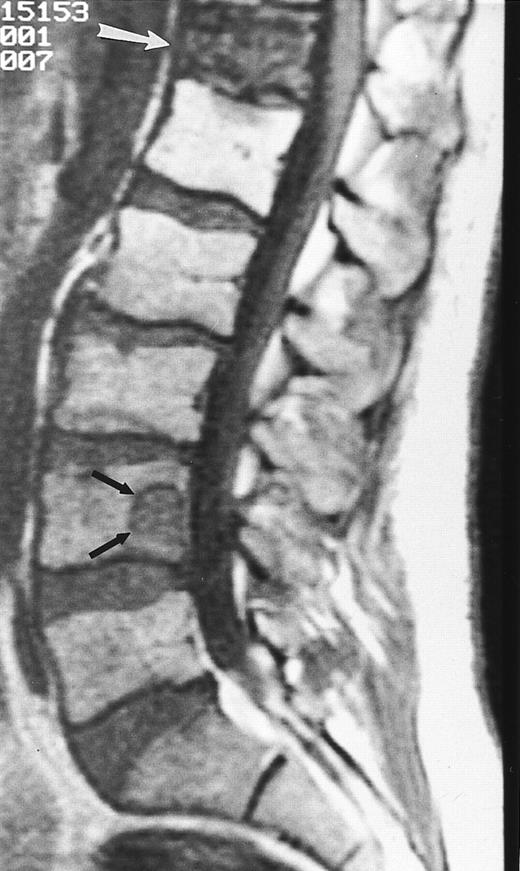

Lymphoma: multifocal bone marrow involvement. Sagittal T1-weighted (500/10, TR/TE) MR image of the lumbar spine shows multiple foci of bone marrow replacement (arrows). This appearance of lymphomatous involvement of the bone marrow is similar to bone metastases. Note extraosseous mass in the presacral space with apparent preservation of the bony cortex and small retroperitoneal lymph node at the level of L2 (arrowheads).